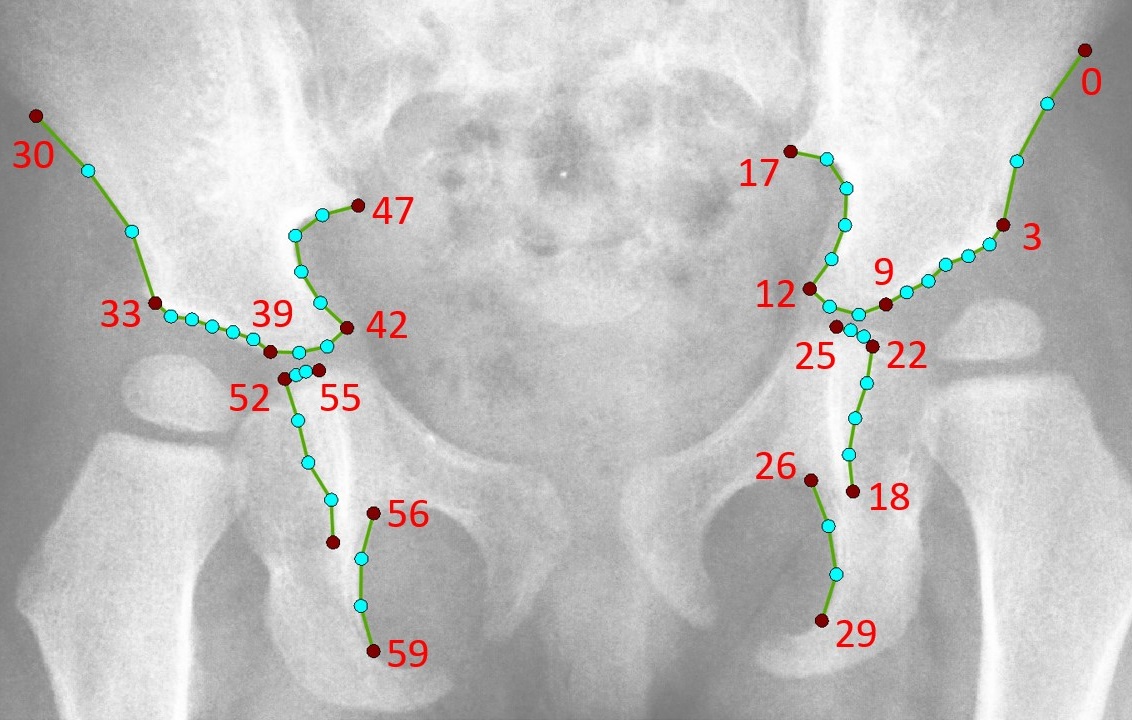

We have developed a software system to automatically calculate Reimer's migration percentage (RMP) and acetabular index (AcI) from children’s hip radiographs. We trained and tested a BoneFinder® module to automatically outline key structures of the proximal femur and pelvis using 102 points based on 450 images. The automatically identified point positions were used to calculate RMP and AcI. The performance of the automatic system was assessed by comparison with measurements taken manually by 5-9 clinicians on two datasets. The initial dataset included 50 hips and the independent replication dataset included 400 hips.

Segmentation example showing the outline of the proximal femur of a 2-year-old and an 18-year-old as well as the outline of the pelvis. Our BoneFinder® module achieved an average point-to-curve-error of 1mm and a point-to-curve-error of less than 2mm for 95% of all 450 images.

The performance of the automatic system showed good agreement with the average manual measurements with inter-correlation coefficients (ICCs) between 0.78 and 0.92. Our results show that the fully automatically obtained AcI and RMP measurements are in agreement with manual measurements obtained by clinical experts.